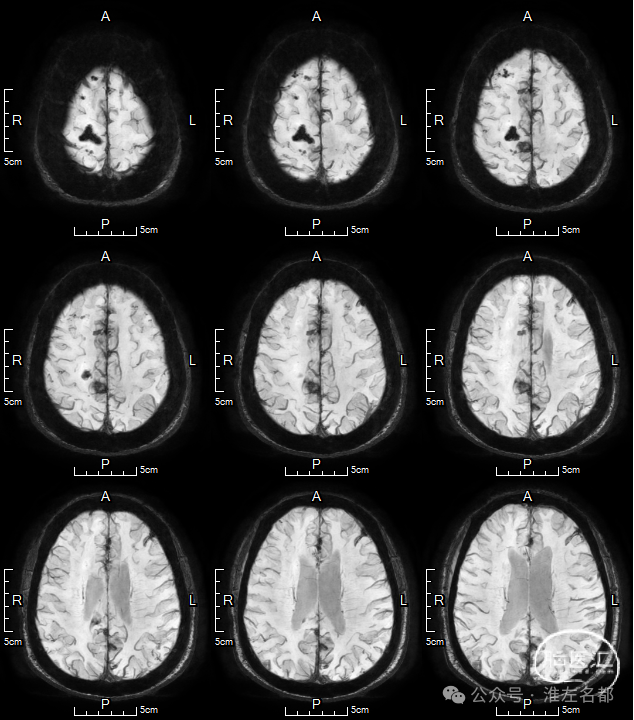

2024-01-23 MRI

DWI:胼胝体膝部和右侧额顶叶皮质多发急性梗死高信号。

SWI:右侧额顶叶皮质梗死灶渗血低信号;前纵裂池内可见少量蛛网膜下腔出血低信号。

3D-TOF-MRA:右侧大脑前动脉A2段管腔未见明确异常。